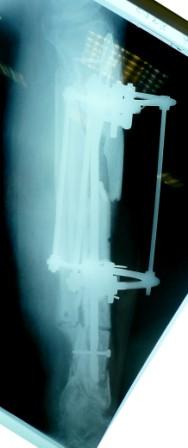

- Была выполнена репозиция в аппарате (рис1)

Имя     : Рис 1 После репозиции перед переходом на Штифт (1).JPG

Тип     : image/jpeg

Размер  : 20022 байтов

Описание: отсутствует

Url     : http://weborto.net:8080/pipermail/ortho/attachments/20090405/a3dc024e/attachment-0011.jpeg

Имя     : Рис 1 После репозиции перед переходом на Штифт (2).JPG

Размер  : 17201 байтов

Url     : http://weborto.net:8080/pipermail/ortho/attachments/20090405/a3dc024e/attachment-0012.jpeg